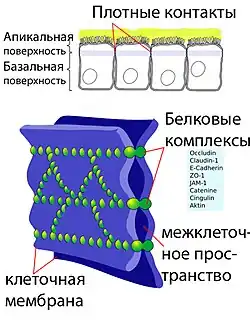

Плотные контакты

Эндотелиальные клетки сосудов мозга плотно прилегают друг к другу. Между их стенками образуются так называемые плотные контакты, роль которых в обеспечении ГЭБ состоит в том, что они предотвращают проникновение в ткань мозга различных нежелательных веществ из кровеносного русла[45][46]. Плотные контакты между эндотелиальными клетками блокируют межклеточный (парацеллюля́рный) пассивный транспорт[47][48][49]. При этом блокируется парацеллюлярный транспорт веществ как из кровеносного русла в ткань мозга, так и в обратном направлении — из мозга в кровь[29].

Большое количество трансмембранных белков, таких как окклюди́н, разнообразные клауди́ны и замыкательные адгезионные молекулы связывают латеральные отделы клеточных стенок между собой, участвуют в формировании плотных контактов и делают возможным межклеточный транспорт и обмен веществ[50]. Основными белками, обеспечивающими адгезию эндотелиальных клеток и формирование плотных контактов, являются клаудин-5 и клаудин-12[51]. Нокаут гена CLDN5, ответственного за синтез белка клаудина-5, приводил у экспериментальных мышей к тому, что их ГЭБ становился проницаемым для молекул с молярной массой до 800 г/моль. Такие генетически изменённые животные умирали через несколько часов после рождения[52].